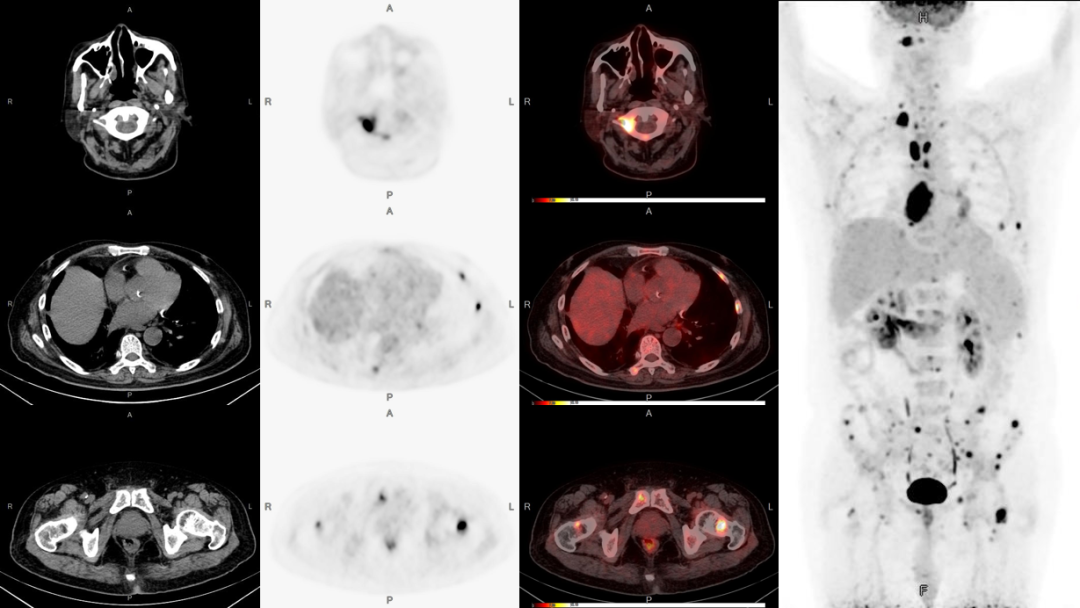

病例2:男性,51歲,反復(fù)咳嗽無痰半年余;發(fā)現(xiàn)左側(cè)鎖骨內(nèi)腫塊數(shù)月余。

3、雙股骨上段轉(zhuǎn)移可能。